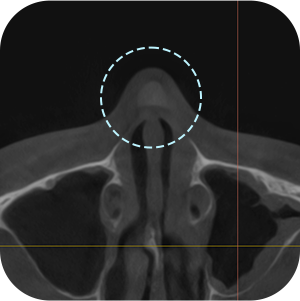

ตรจสอบผนังกั้นจมูก และโพรงจมูกภายใน

ตรจสอบตำแหน่งที่แน่นอน ของซิลิโคนเดิม

จำเป็นต้องถ่าย CT จมูกก่อนผ่าตัด ?

Aยิ่งเป็นกรณีผ่าตัดแก้ไข ก็ต้องยิ่งวิเคราะห์ละเอียดขึ้น!

การวิเคราะห์อย่างละเอียด จำเป็นอย่างมากต่อ การผ่าตัดแก้ไขจมูก

วิเคราะห์ได้อย่างละอียด

จากการถ่าย 3D-CT! - 03